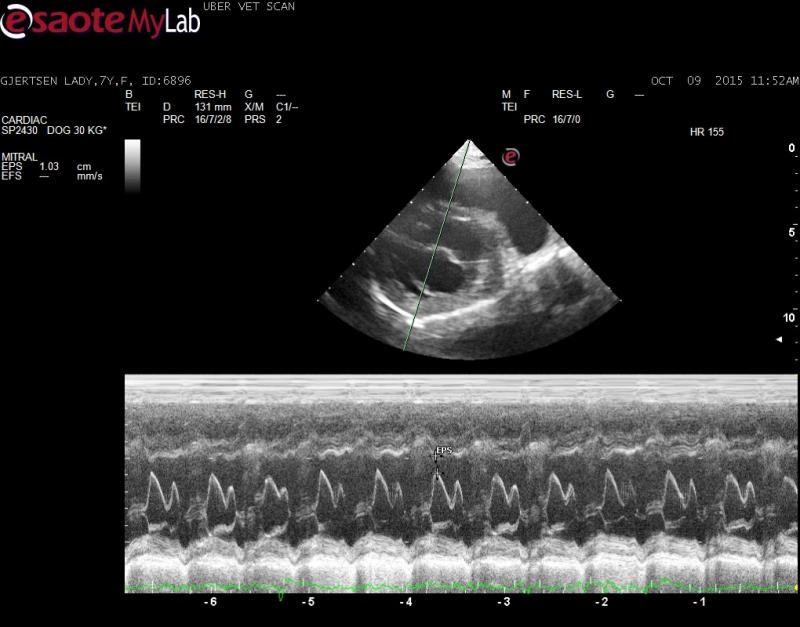

– echo showed normal LV parameters (no eccentic hypertrophy documented) however EPSS is elevated and FS% decreased

Innapropriate wall thickening with dilated L ventricular chamber elevated EPSS and poor FS to me indicates cardiomyopathy. Consider a mitral inflow study to get some sort of idea of L atrial pressure. I am suprised the L atrium is not more dilated.

The mitral inflows were wnl and the LV chamber and walls were also wnl when using the Cornell reference ranges and the GD breed specific tables but the FS% and EPSS sure points toward occult DCM to me.